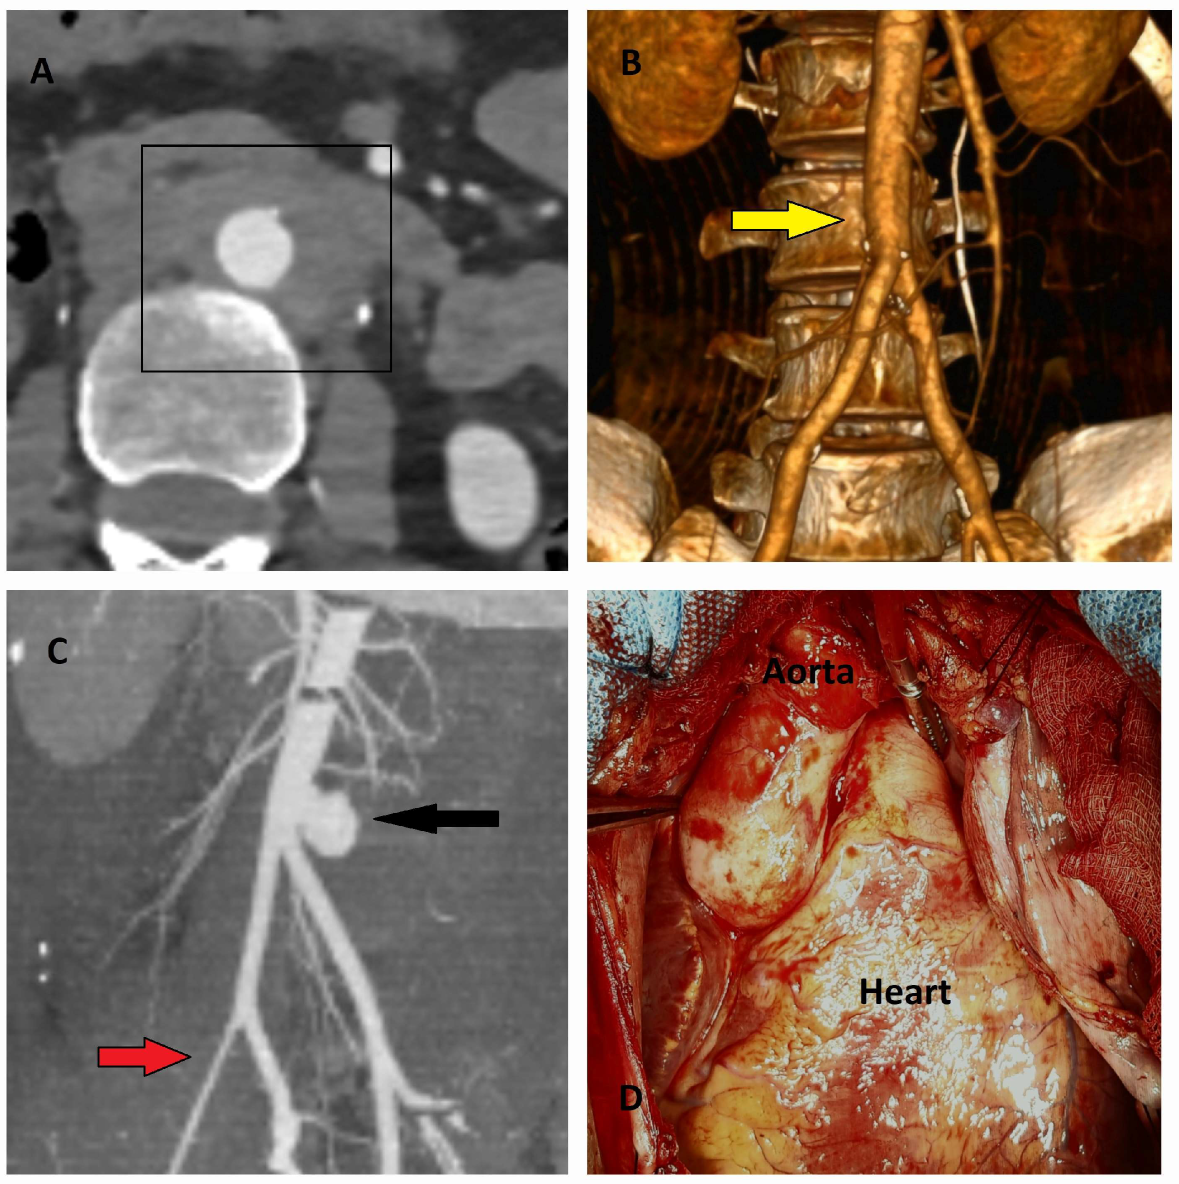

5.2.3. Computed Tomography